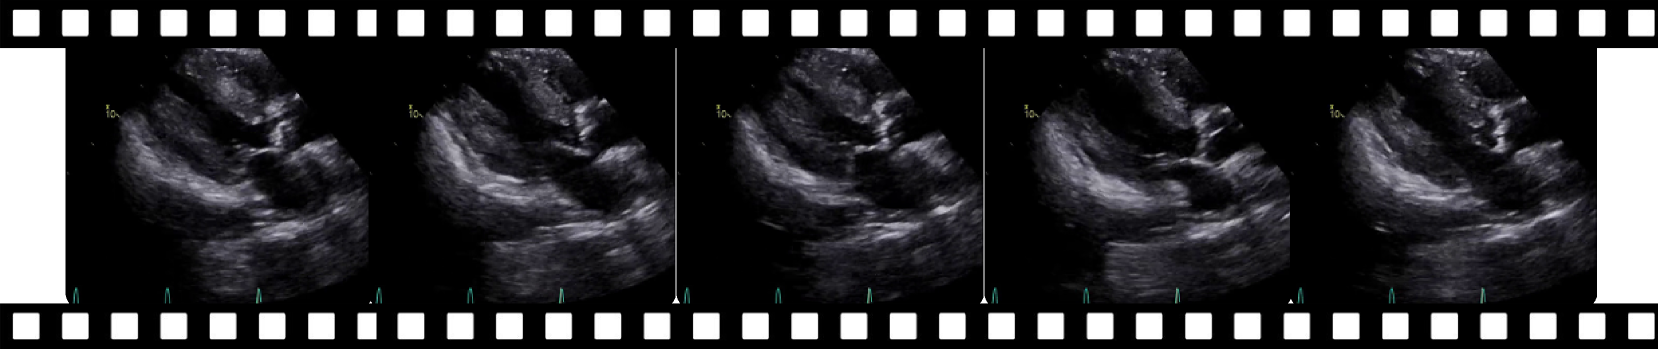

MIMICEchoQA.

This benchmark is derived from a publicly available echocardiogram video dataset called MIMIC-IV-ECHO (Gow et al., 2023). We paired each study in the dataset with the nearest available discharge summary following the video, provided the time difference between the study date and discharge date was within 7 days, removing studies without discharge summary within the timeframe. From the matched discharge summaries, we extracted the transthoracic echocardiography (TTE) and ECHO sections as proxies for cardiologist reports. These sections typically contain diagnostic information such as ejection fraction and cardiac abnormalities.

To standardize the input format, we converted each DICOM file into an .mp4 video. The corresponding cleaned reports were then processed using GPT-4o to generate multi-turn, closed-ended Q/A pairs. However, this automated process occasionally produced questions referencing anatomical structures not visible in the associated videos. To mitigate this, we employed a view classification model (Vukadinovic et al., 2024) to label each video with its specific echocardiographic view (e.g., A3C, A4C), allowing us to filter out unanswerable questions based on view-specific visibility constraints.

Because the view classifier is not perfectly accurate, and to ensure clinical validity, two board-certified cardiologists manually reviewed the generated Q/A pairs. This review identified and removed questions that remained unanswerable given the visual content of the videos, even after automated filtering. This process resulted in a final set of 620 high-quality, clinically valid Q/A pairs. The prompt used for Q/A generation is provided in Section C.6, and qualitative examples from the dataset are shown in Section D.3.